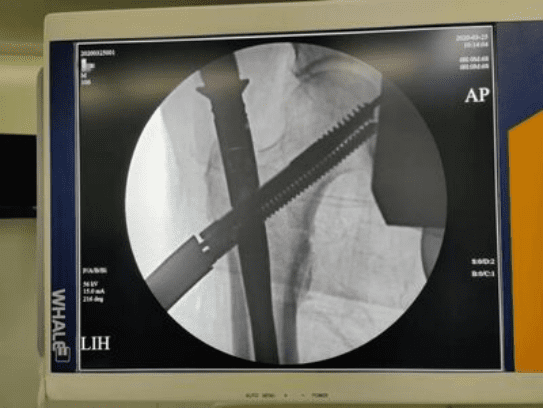

The whole operation was very smooth, and it took less than 30 minutes for the skin incision to suture. On the first day after the operation, the patient achieved early mobilization of the affected limb, and on the third day, the patient got out of bed. Canwell Tri-max with excellent mechanical design to help patients quickly recover. This operation effectively avoided the complications caused by conservative treatment and created good conditions for the recovery of limb function.

Intertrochanteric fracture is a common type of fracture in clinical practice, and it mostly occurs in the elderly. Especially with the aging of the social population and the frequent occurrence of traffic accidents, the incidence of intertrochanteric fractures is on the rise. At present, there are many methods for treating intertrochanteric fractures, but the Canwell Medical Tri-Max proximal femoral intramedullary nail is one of the best choices for the treatment of intertrochanteric fractures. There are three proximal locking methods for one main nail. Intertrochanteric fracture has the characteristics of small trauma, short operation time, firm fixation, high fracture union rate, satisfactory clinical effect, and few complications.